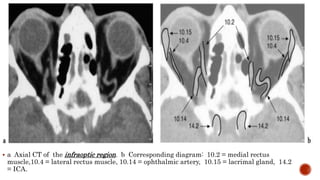

 a Axial CT of the infraoptic region. b Corresponding diagram: 10.2 = medial rectus

muscle,10.4 = lateral rectus muscle, 10.14 = ophthalmic artery, 10.15 = lacrimal gland, 14.2

= ICA.